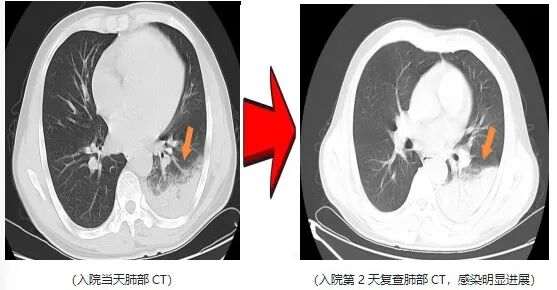

近日,一名爱鸟人士因持续高热、剧烈咳嗽,紧急就诊并收治于杭州萧山区中医院呼吸内科。入院后予以常规抗感染治疗2天,患者高热症状仍反复,最高体温升至40.5℃,伴干咳气促、夜间难以入眠,病情进展后更出现咯血及呼吸衰竭表现。

鉴于患者病情呈重症化趋势,在排除急性肺栓塞等支气管镜检查禁忌证后,医院呼吸内科团队第一时间为患者完善支气管镜检查,同步采集肺泡灌洗液行病原学宏基因组测序,最终锁定致病“元凶”—— 鹦鹉热 衣原体 ,该病原体正是源于患者饲养的宠物鹦鹉。

明确病因后,医护团队予针对性特效药物干预。仅2天后,患者体温恢复正常,干咳气促、咯血及呼吸衰竭等症状均显著缓解,后续顺利康复出院。